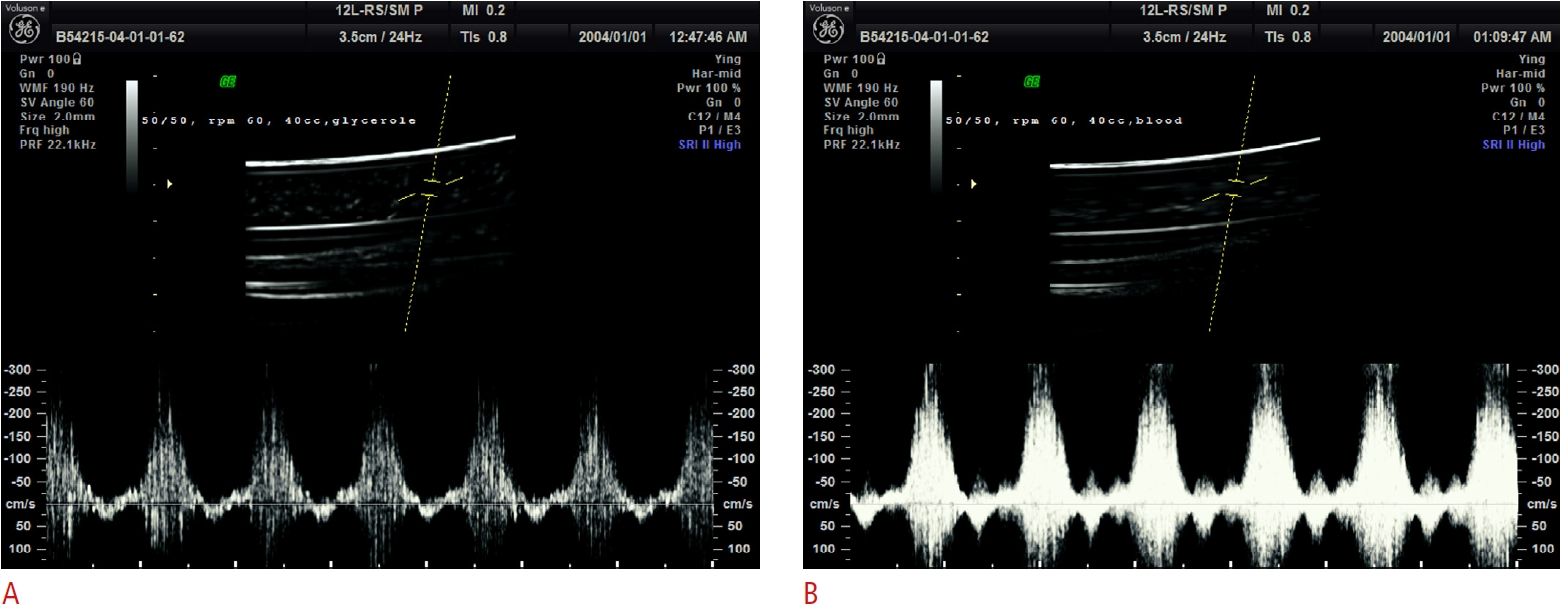

Spatiotemporal blood viscosity by local hematocrit under pulsatile flow: Whole blood experiments and computational analysis

Computers in Biology and Medicine, Nov 2025